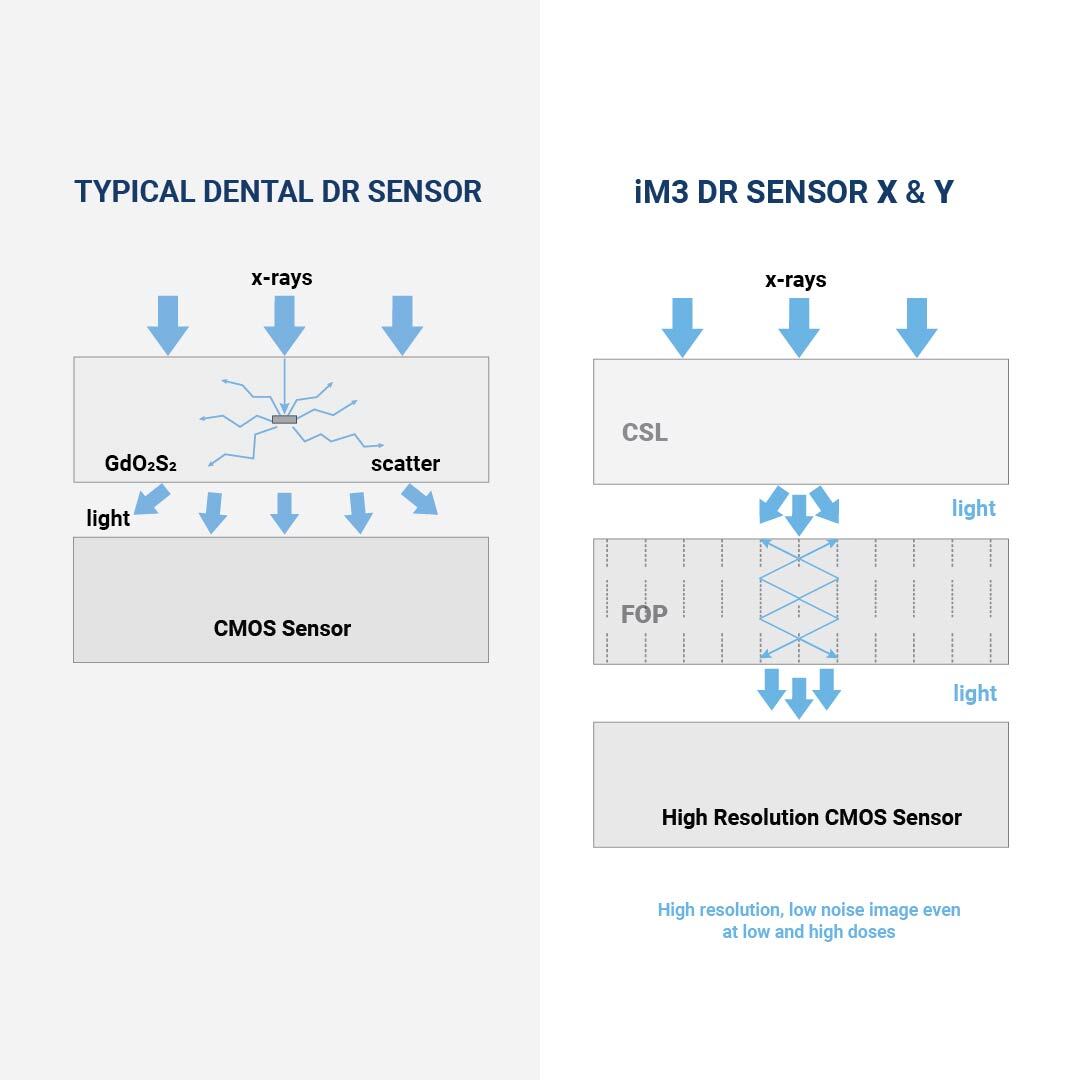

El iM3 DR Sensor Y utiliza un scintilador de Csl en lugar de los sensores basados en Gadox más comunes, lo que resulta en una resolución mucho mayor y menos ruido.

Con una impresionante resolución de 20 lp/mm (pares de líneas por milímetro), supera la resolución típica de 12 lp/mm que se encuentra en los sensores convencionales. Este nivel elevado de detalle y claridad en las imágenes capturadas permite evaluaciones más precisas y completas de la patología dental.

Transmisión rápida de imágenes con CMOS

La moderna tecnología CMOS del DR Sensor X garantiza una transmisión rápida de imágenes con alta resolución. La nueva capa de scintilador reduce la dispersión y concentra la luz, lo que influye positivamente en la calidad de la imagen.